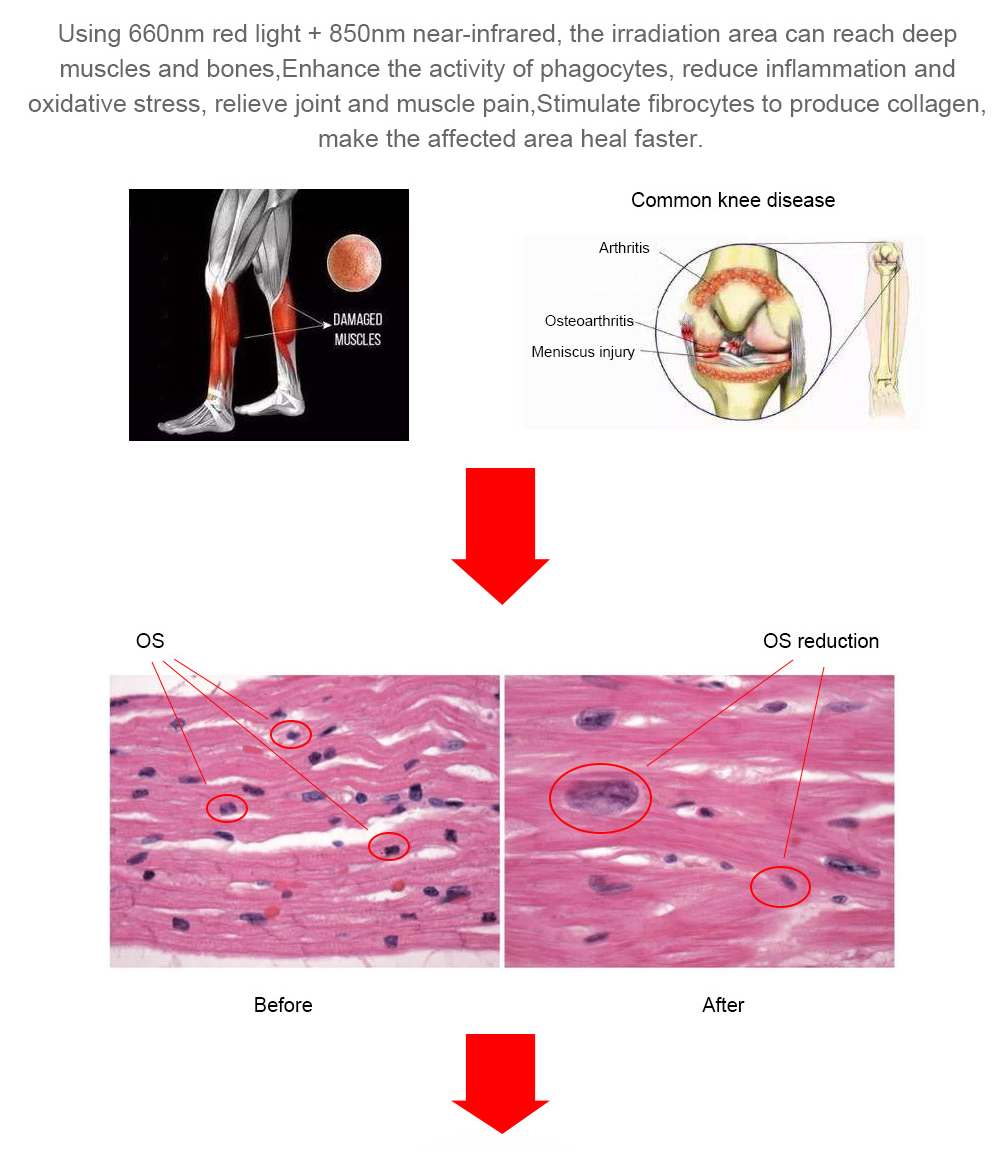

Red light therapy is also known as low-level laser therapy (LLLT). It uses low energy light emitting diodes (LEDs) or lasers as an alternative therapy for pain relief, or to promote good cell functions.

The principle of red light therapy can be thought of as like a human version of the way plants photosynthesize. It is thought that certain wavelengths of light can enhance the functioning of mitochondria, which are the organelles in a cell which take in nutrients and break them down to create energy molecules for the cell. By enhancing the cellular respiration, it will improve the functioning of the whole cell.